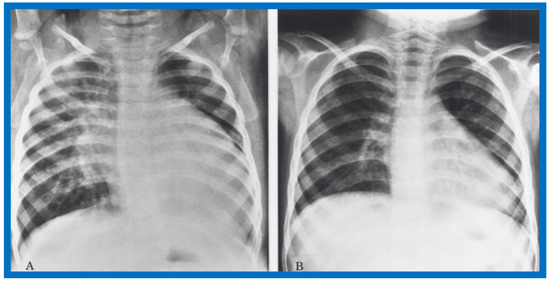

Examples of improvement in LV dimension on echo studies are shown in Figure 40 and Figure 41. The cardiac size and pulmonary venous congestion on chest roentgenograms improved in the hydralazine group (Figure 42 and Figure 43). No significant changes in any of these parameters occurred in the control group.

Figure 40.

Selected M-mode recording from the parasternal short axis view of the left ventricle (LV) prior to (A) and following (B) hydrazine therapy. Note the significant improvement in the LV size and function.

Figure 41.

Selected M-mode recording from the parasternal short axis view of the left ventricle (LV) prior to (A) and following (B) hydrazine therapy from a different infant. Also, note the significant improvement in the LV size and function.

Figure 42.

Antero-posterior view of chest x-rays prior to (A) and following (B) hydralazine therapy. Moderate cardiomegaly and pulmonary venous congestion were seen prior to therapy (A) which improved remarkably after therapy (B).

Figure 43.

Antero-posterior view of chest x-rays prior to (A) and following (B) hydralazine therapy from a different infant. Moderate cardiomegaly with pulmonary venous congestion was seen prior to therapy (A) which improved remarkably after therapy (B), similar to that seen in Figure 42.